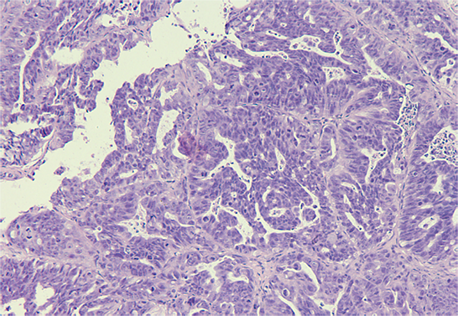

PDX Model (MED-PDX-001C H&E (10X))